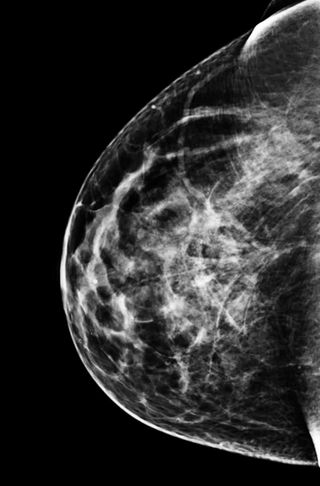

BREAST DENSITY ACCORDING TO THE ACR CLASSIFICATION

ACR breast density refers to the classification of breast density according to the Breast Imaging Reporting and Data System (BI-RADS) developed by the American College of Radiology (ACR). ACR breast density is classified into four categories: Category A: fatty tissue that represents less than 25% of the breast. Category B: fatty tissue that represents between 25% and 50% of the breast. Category C: fatty tissue that represents between 50% and 75% of the breast. Category D: fat